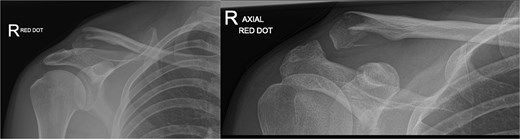

A 30-year-old male presented with an unstable lateral clavicle fracture and skin tenting after a rugby injury. Imaging revealed a Neer type IV equivalent fracture (Fig. 3). He underwent open reduction and internal fixation with coracoid exposure and TightRope placement, reinforced with fiber-wire. Postoperative recovery included sling immobilization followed by pendular exercises. Despite delayed radiological union, he achieved full range of motion and strength by three months, with only mild, asymptomatic clavicular prominence. He returned to physically demanding work without restrictions, and final imaging confirmed union (Fig. 4A–C).

Radiographs of second case showing a displaced lateral end clavicle fracture with deformity and dorsal displacement.